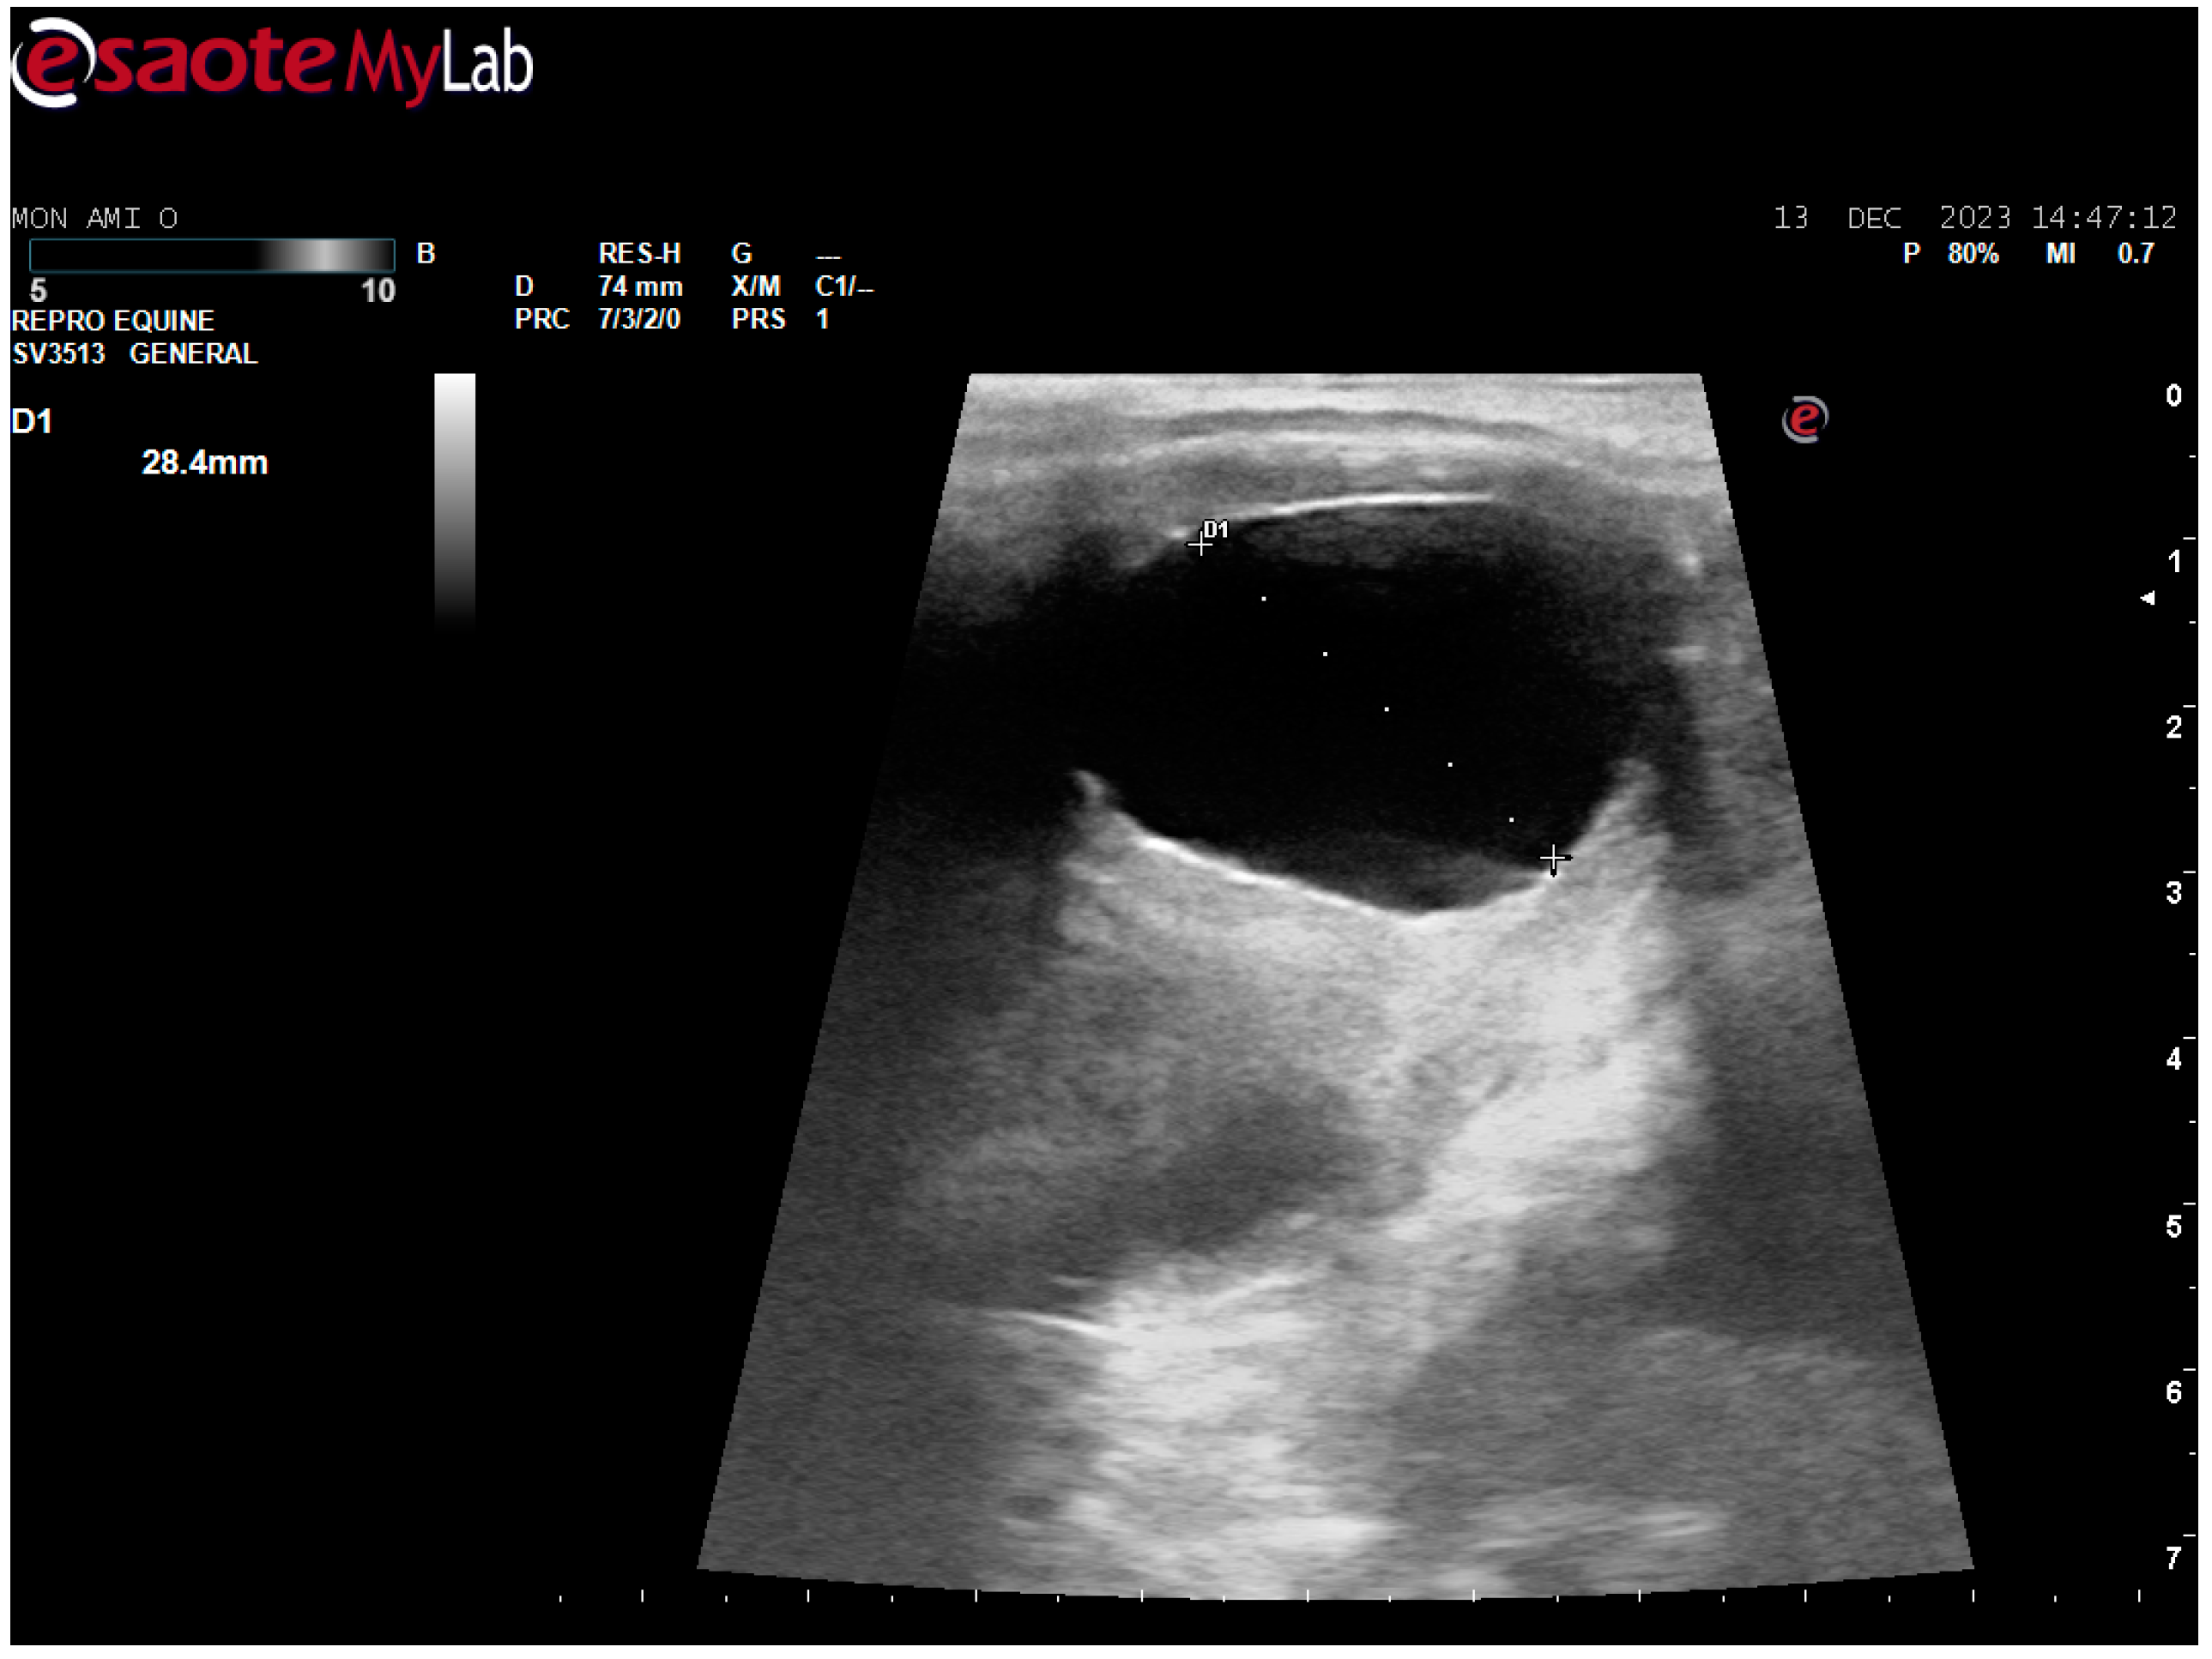

After surgery, the mare’s reproductive system was investigated. Ultrasonographically, slight uterine edema (grade 1 out of 5) and hyperechoic particles (Figure 2), suspected as air in the uterus, were observed. The left ovary was normal in size and echogenicity, present with some 10 to 28.4 mm follicles (Figure 3 and Figure 4). Due to poor perineal conformation, the mare had pneumovagina. Caslic’s vulvoplasty was performed.

Figure 3. Left ovary, present with some >10 mm follicles. Ultrasonographic picture post surgery.

Animals 14 01307 g003

Figure 4. Left ovary, present with 28.4 mm follicle follicles. Ultrasonographic picture post surgery.

Animals 14 01307 g004